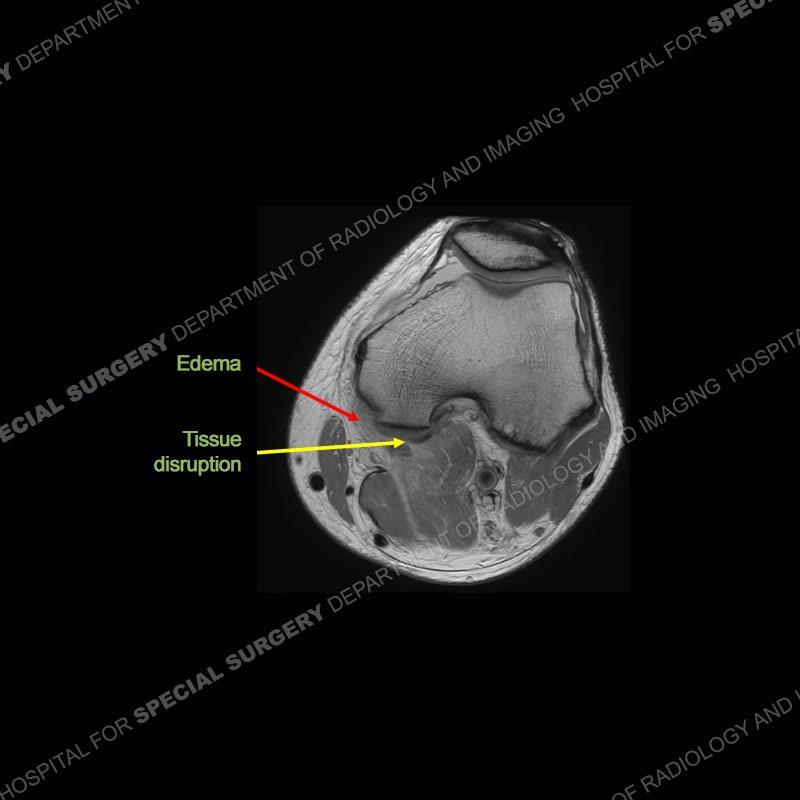

The radiographs show degenerative change of the medial compartment and a varus knee, but they are not germane to this case. No acute bony injury is present. The MRI shows edema of the posterior medial knee/soft tissue and a focal area of a partially disrupted low signal structure. The details are kept at a minimum in the findings of this case on purpose.

Diagnosis: Partial Disruption Medial Head Gastrocnemius (MHG)

Fourth, use all imaging planes and different pulse sequences to make your diagnosis. The edema highlighted in this case can be seen as the obscuration of fat on the PD images but is much easier to perceive as the high signal on the IR pulse sequences. The actual disruption of the MHG myotendinous junction is only able to be seen on the axial images. On the sagittal and coronal images, we get a sense something is wrong but hard to be exact. Lastly, when you look at a study and something just seems off (as I would say the sagittal and coronal images do with that dark band of tissue posteriorly), listen to yourself and go through the study slowly and meticulously. Most of the time you will find you were right, and something indeed is present.